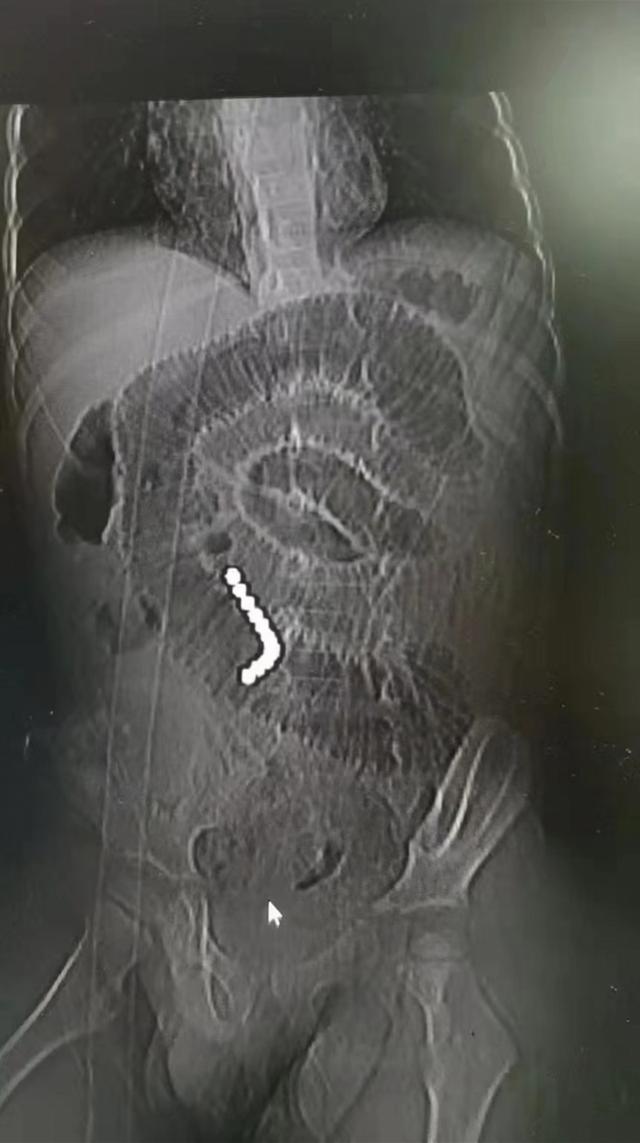

小杰9月3日凌晨被转入珠江医院小儿外科。“当时患儿腹痛腹胀的症状依然很明显,腹部影像检查结果很清晰,腹腔内足足有11颗并排的珠子”,珠江医院小儿外科主任杨六成教授说,虽然肚子疼,但孩子入院时还能自己走,看着并不严重,但医生们知道这时已经很危险,就向父母说明情况,紧急安排急诊手术。

影像学检查发现了小杰体内排成一排的磁力珠。通讯员供图